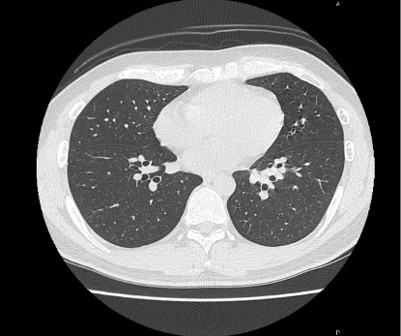

CT撮影室

X線を使って体を輪切りにした画像を構成します。

当院では80列マルチスライスCTが稼働しており、数秒の息止めで胸部から骨盤まで撮影することができ

ます。また被ばくを低減させる機能も搭載されています。